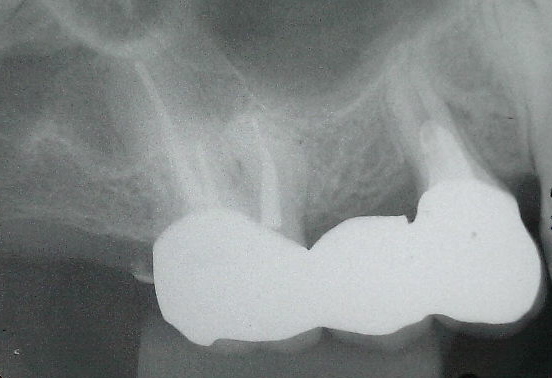

治療前

左のX線の矢印で示してある歯が割れていたので、一旦歯を抜いてきれいにしました。